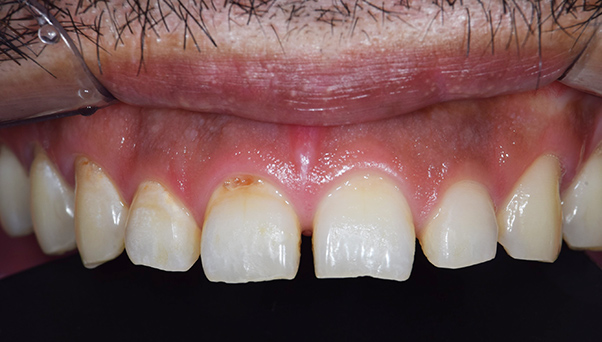

年齢・性別 40代・男性

主訴 銀歯を白くしたい

治療方針 金属を使った詰め物、被せ物を外して、セラミックでの詰め物、被せ物にやりかえたいというご要望がありました。

奥歯はほとんどの歯に詰め物が入っていましたので、まずは奥歯から噛み合わせをきちんと作ってから前歯の被せ物をやりかえていく方針としました。

また、左下の奥から1番目の歯は虫歯が大きいことをレントゲンで確認できており、神経を取り除かねばならない可能性が高いことを説明してから、治療をおこなっていきました。

治療内容 左下の奥から2番目の歯は、やはり神経を取り除く必要がありました。その他の奥歯の部位は詰め物のやり変えのみですみました。 前歯は金属の土台(メタルコア)も取り除き、セラミックとジルコニアでできた被せ物を入れていきました。

治療費 合計:903,100円

(内訳)

セラミックインレー:55,000円×11本

ファイバーコア:16,500円

仮歯:3,300円×2本

ジルコニアボンドクラウン:165,000円

ジルコニアステインクラウン:110,000円

治療期間 4ヶ月

治療のリスク・副作用 詰め物を入れた後も冷たいものなどで染みることがあります。 今回のケースのように、銀歯の下では虫歯になっていることがおおく、神経を取り除かねばならないことが多々あります。